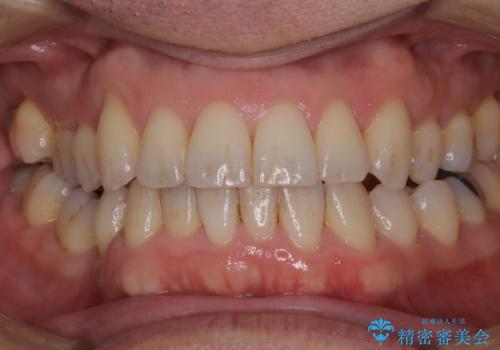

紅茶のステインをきれいにしたい

- 毎日紅茶を飲むため、歯のステインが気になるためキレイにしたいとのことでした。

PMTC60分コースを行いました。